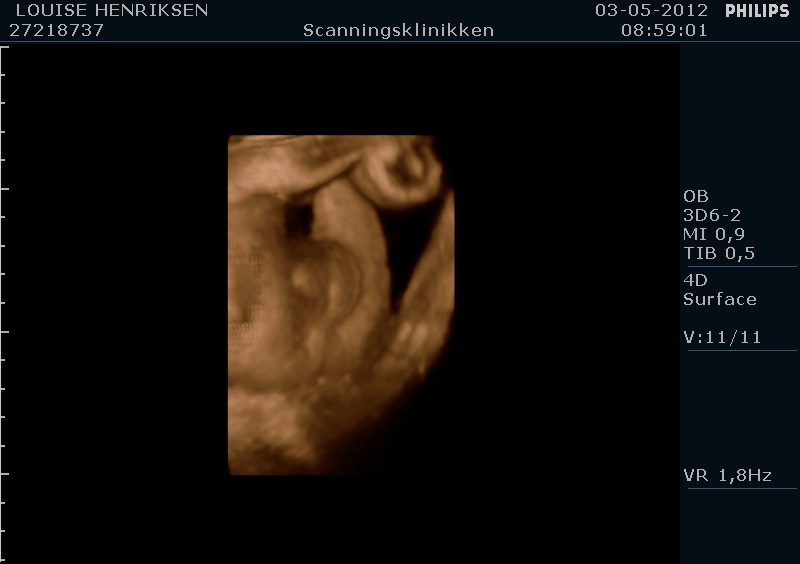

I dag skulle manden overraskes med en 4 d scanning.... og hans far var også med det var også en overraskelse, samt den lille prins....han fik bind for øjene og vi kørte mod scanning klinikken.... vi fik nogle gode sekvenser af bettemanden.. men han fylder en del derinde nu, så billederne blev ikke voldsomt gode.. men nogle fik vi dag...jeg skulle i morgen være 32 fulde uger.. mne scanningen i dag vidste34+4 dage yiarks.... jeg skal til at være færdig med den bachelor..... han vejede efter målene 1871 gram.....

så han var en fin basse...